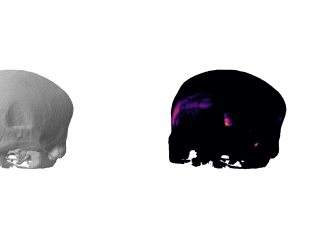

healthy

We show some slices with examples of ICH in \figurereffig:qualitative_ich as well as surface renderings of scans of subjects with cranial fractures in \figurereffig:qualitative_fractures. (As a reference we also included the same examples for the AE in Appendix D in \figurereffig:qualitative_ich_ae.) It is noticeable that the reconstruction error is high where there is an anomaly. The reconstruction error generally seems to continuously depend on the amount of the patch that is anomalous, as the error maps generally seem to be rather smooth.

The performance for the models used for \figurereffig:qualitative_ich and LABEL:fig:qualitative_fractures are shown in \figurereffig:roc_performance. We observe see that the detection of fractures is the more challenging task for our method than the detection of ICH. This might be due to the smaller number of scans available to evaluate it on (see Appendix B). To put these results in context we provided a table with the inter rater agreement on these tasks in Appendix B: The performance in terms of AUROC is around lower than the average raters.

fig:qualitative_fractures